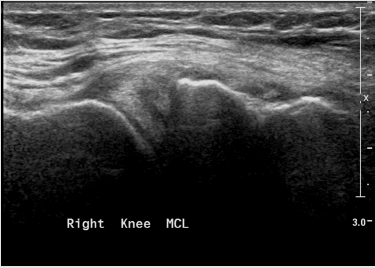

Figure 11: Medial collateral ligament partial tear - thickening, hypoechoic proximal part of the ligament with fluid around it.